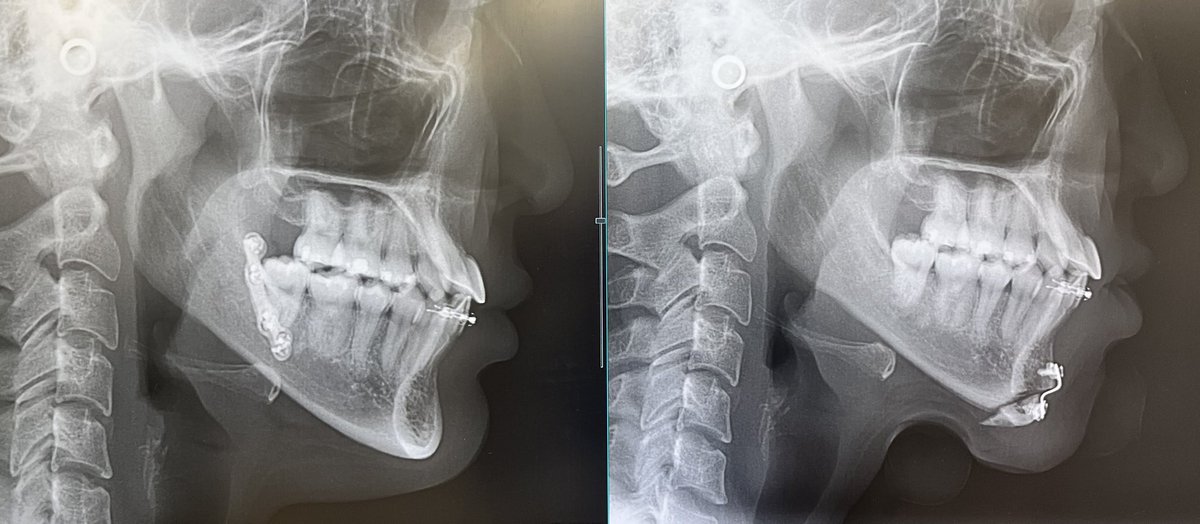

←術前 術後→ レントゲン見せてもろた🥺 骨だけでみると短くなってる、、 顎長く見えるのは腫れのせいで、オトガイのプレ除去したらさらに滑らかになると思います〜って言われた とりあえずDT中だから病むのやめる😭‼️早く腫れ引け、、

←術前 術後→

レントゲン見せてもろた🥺

骨だけでみると短くなってる、、

顎長く見えるのは腫れのせいで、オトガイのプレ除去したらさらに滑らかになると思います〜って言われた

とりあえずDT中だから病むのやめる😭‼️早く腫れ引け、、